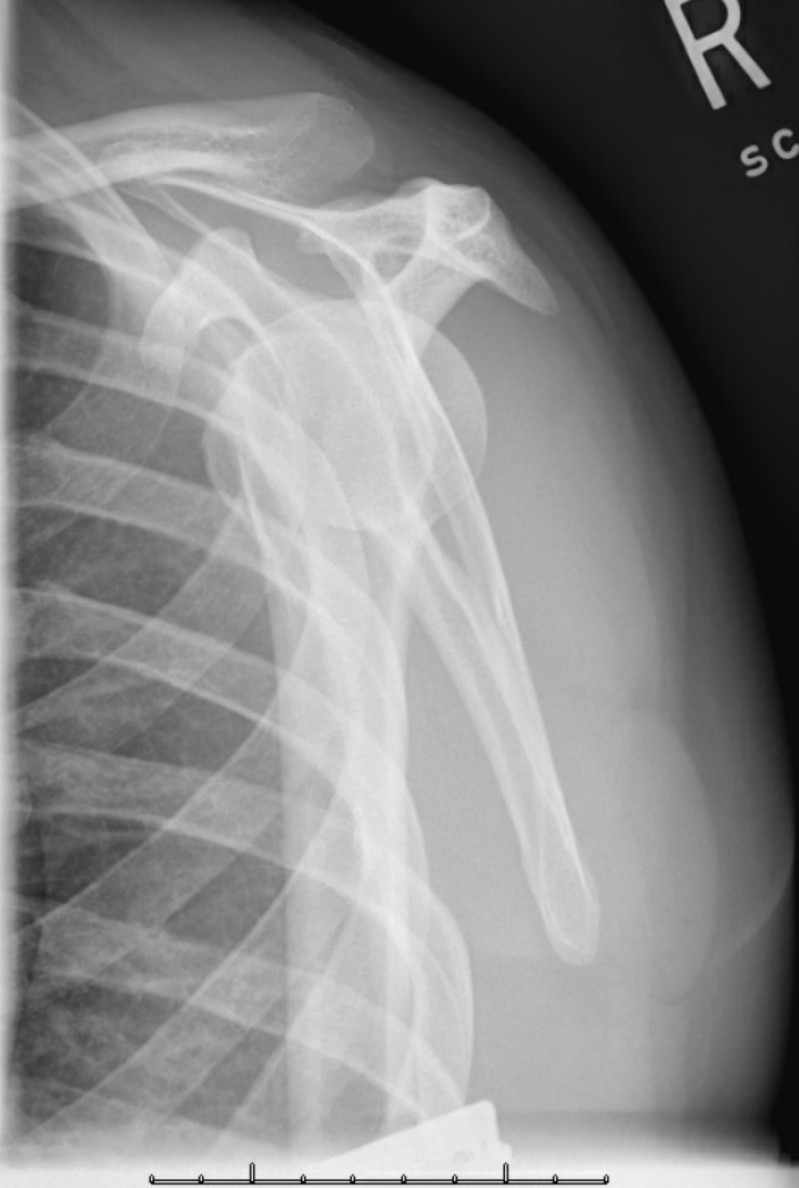

X Ray Posterior Shoulder Dislocation . Posterior dislocation may be missed initially on frontal radiographs in 50% of cases, as the humeral head appears to be almost normally aligned with the glenoid 1,2. Electrocution is a classic but uncommon cause of posterior. Anteroposterior radiograph shows luxatio erecta, or inferior dislocation of the shoulder. The arm is abducted, elevated, and fixed. The axillary lateral view is the most accurate radiographic image to diagnose a posterior shoulder dislocation. Posterior shoulder instability and dislocations are less common than anterior shoulder instability and dislocations, but are much more commonly missed. In adults, convulsive disorders are the most common cause. The humeral head is subcoracoid in. This view eliminates most overlying bony and soft tissue.

In adults, convulsive disorders are the most common cause. The arm is abducted, elevated, and fixed. This view eliminates most overlying bony and soft tissue. The axillary lateral view is the most accurate radiographic image to diagnose a posterior shoulder dislocation. The humeral head is subcoracoid in. Electrocution is a classic but uncommon cause of posterior. Posterior dislocation may be missed initially on frontal radiographs in 50% of cases, as the humeral head appears to be almost normally aligned with the glenoid 1,2. Anteroposterior radiograph shows luxatio erecta, or inferior dislocation of the shoulder. Posterior shoulder instability and dislocations are less common than anterior shoulder instability and dislocations, but are much more commonly missed.

Posterior Shoulder Dislocation • LITFL • Trauma Library X Ray Posterior Shoulder Dislocation Posterior dislocation may be missed initially on frontal radiographs in 50% of cases, as the humeral head appears to be almost normally aligned with the glenoid 1,2. In adults, convulsive disorders are the most common cause. This view eliminates most overlying bony and soft tissue. Posterior shoulder instability and dislocations are less common than anterior shoulder instability and dislocations, but. X Ray Posterior Shoulder Dislocation.